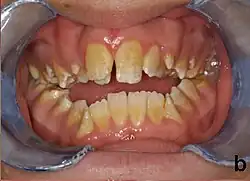

Die Amelogenesis imperfecta (von Altenglisch: amel „Schmelz“ und Altgriechisch: γένεσις (genesis) „Entwicklung“[1] sowie lateinisch imperfectus ‚unvollendet‘),[2] auch angeborene Zahnschmelzhypoplasie genannt, ist eine genetisch bedingte Erkrankung, bei der es zu einer Störung der Zahnschmelzbildung kommt. Der Zahnschmelz besteht hauptsächlich aus Mineralien, deren Aufbau und Struktur im Zahn von Proteinbestandteilen reguliert wird. Die Amelogenesis imperfecta beruht auf einer Fehlfunktion der Proteine im Zahnschmelz. Es handelt sich in der Hauptsache um die vier Proteine Ameloblastin, Enamelin, Tuftelin und Amelogenin. Bei den Betroffenen imponiert eine gelbliche bis grau-braune Verfärbung der Zähne. Die Zähne haben ein erhöhtes Risiko der Kariesbildung und sind besonders temperaturempfindlich. Jeder Zahn kann betroffen sein. Bei Menschen mit dem Williams-Beuren-Syndrom kommt die Zahnschmelzhypoplasie überdurchschnittlich häufig vor.